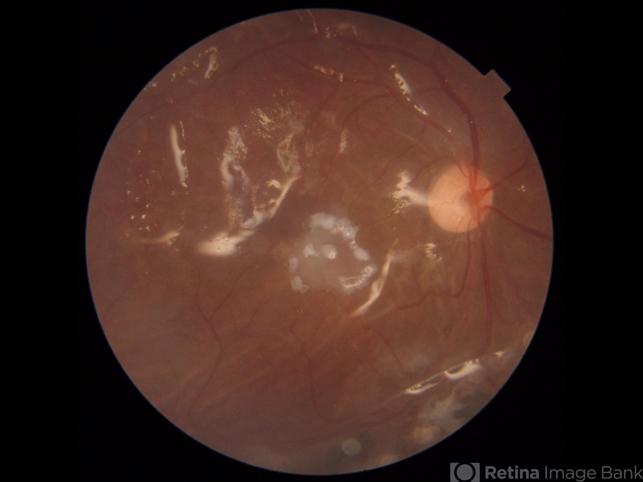

- macular hole, autograft

- 20-year-old boy presented with recurrent retinal detachment post silicone oil removal with a macular hole. During surgery a retinal graft was created from the detached retina and positioned on the macular hole. silicone oil was injected at the end of surgery. One can see the diathermy marks on all sides of the edges of the graft.